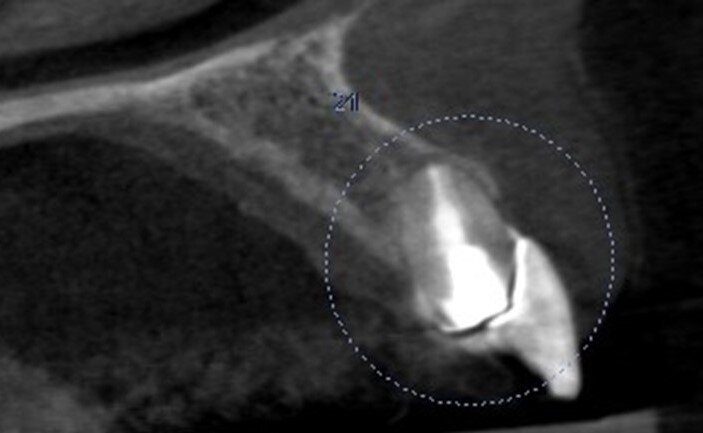

A 53-year-old female patient presented to the office with a fractured left central incisor which had been repeatedly bonded to a ceramic crown (Figs. 1 & 2). Anamneses and examination established good systemic and oral health, a well-balanced occlusion and no smoking habits. Cone beam computed tomography (CBCT) and a periapical radiograph showed external root resorption with very limited insertion into the alveolar bone, insufficient for adequate conventional intra-radicular post placement (Figs. 3 & 4). Considering that the fractured tooth was in the aesthetic zone, the patient requested restoration in the safest and fastest way possible.

Fig. 4: Pre-op CBCT scan.